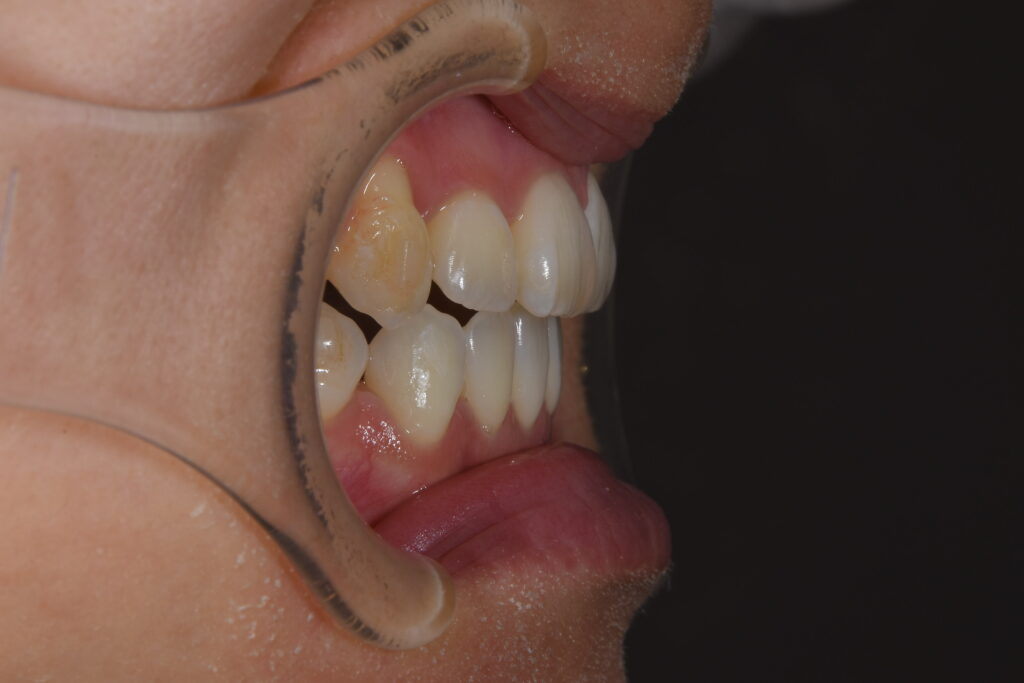

まずは初診時です。

【初診時】

今回ご紹介の患者様の問題点

①叢生(歯のがたつき)→清掃性が悪く将来虫歯・歯周病リスクが高くなる

②開口(奥歯しか噛んでいない)→かみ合わせが原因で、将来的に奥歯が痛くなる

③審美的問題

以上の問題点より、矯正治療を開始致しました。

今回の治療計画は上下小臼歯の抜歯を行いました。

治療装置はインビザライン(マウスピース)です。針金は使用しておりません。